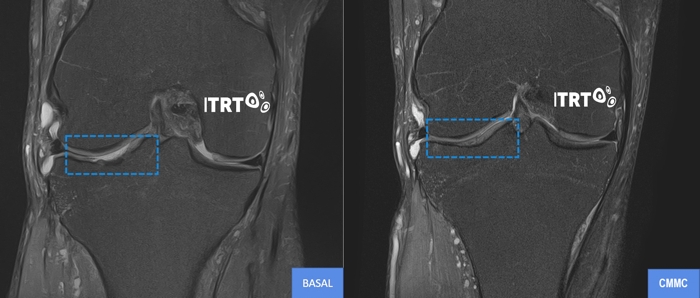

The therapy developed by ITRT has been proven in controlled clinical trials using high-resolution magnetic resonance imaging (T2 mapping) to have the ability to regenerate joint cartilage and avoid the need for costly and uncomfortable prostheses.

Clinical trials have demonstrated that a single dose of Cultured Mesenchymal Stem Cells

is sufficient to unleash regenerative power and heal the injury. The improvement in pain is experienced almost immediately and progresses along with functionality during the first 3 months.

The improvement continues to evolve during the first year and continues over the years, as has been proven in patients treated more than 10 years ago, who have eliminated their injury and regained their lives.